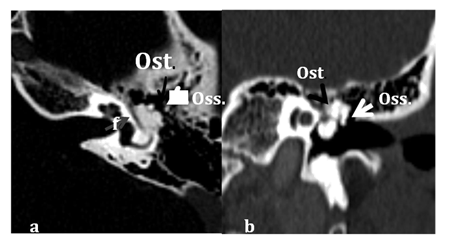

Figure 2 Axial (a) and coronal (b) views displaying Osteoma emanating from superior and medial wall of middle ear cavity, inseparable from Tympanic course of the facial nerve canal (grey arrow). The malleus head, incus body and short process (white arrow) are displaced laterally.

Abbreviations: F, facial nerve canal; OST, osteoma ; OSS, ossicles.